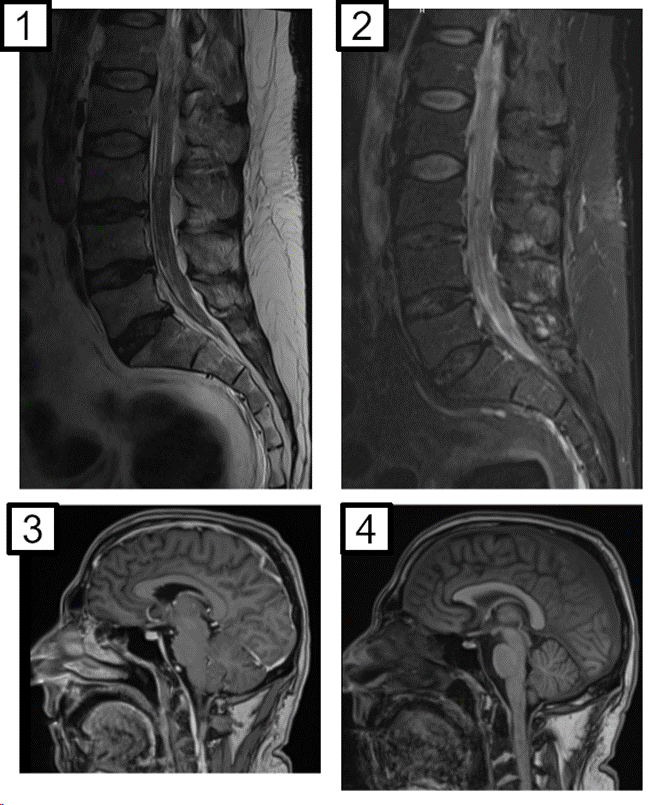

Estudios de imagen. Tomografía cuello-tórax-abdomen-pelvis: esplenomegalia leve. Resonancia magnética de cerebro y columna completa con contraste EV: refuerzo y engrosamiento de las raíces de la cola de caballo, asociado a refuerzo ependimario y de pares craneales con áreas pseudonodulares. Ecografía testicular y fondo de ojo: normales. Ecocardiograma transtorácico, sin hallazgos relevantes.

Figura 1. Resonancia magnética de columna lumbosacra en un corte sagital en secuencia T2 (1) y T1 con contraste EV (2), donde se observa refuerzo y engrosamiento de las raíces de la cola de caballo. En los cortes sagitales de encéfalo en secuencias T1 con contraste (3) y sin (4) se observa realce paquimeníngeo a predominio frontal.